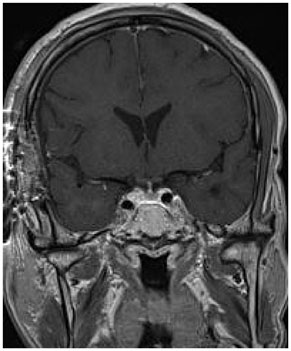

- Granular cell tumors (GCTs) have been reported in various tissues, especially the skin and subcutaneous soft tissue of the head and neck. We report a 60-year-old man who presented with intermittent headache and dizziness for 3 months, but no other neurological symptoms. Magnetic resonance imaging (MRI) showed the presence of a mass in the pituitary stalk, and contrast-enhanced MRI showed nodular enhancement in this region. The lesion was completely excised microscopically via a frontotemporal (pterional) approach. On pathological examination, a final diagnosis of a typical GCT was made.